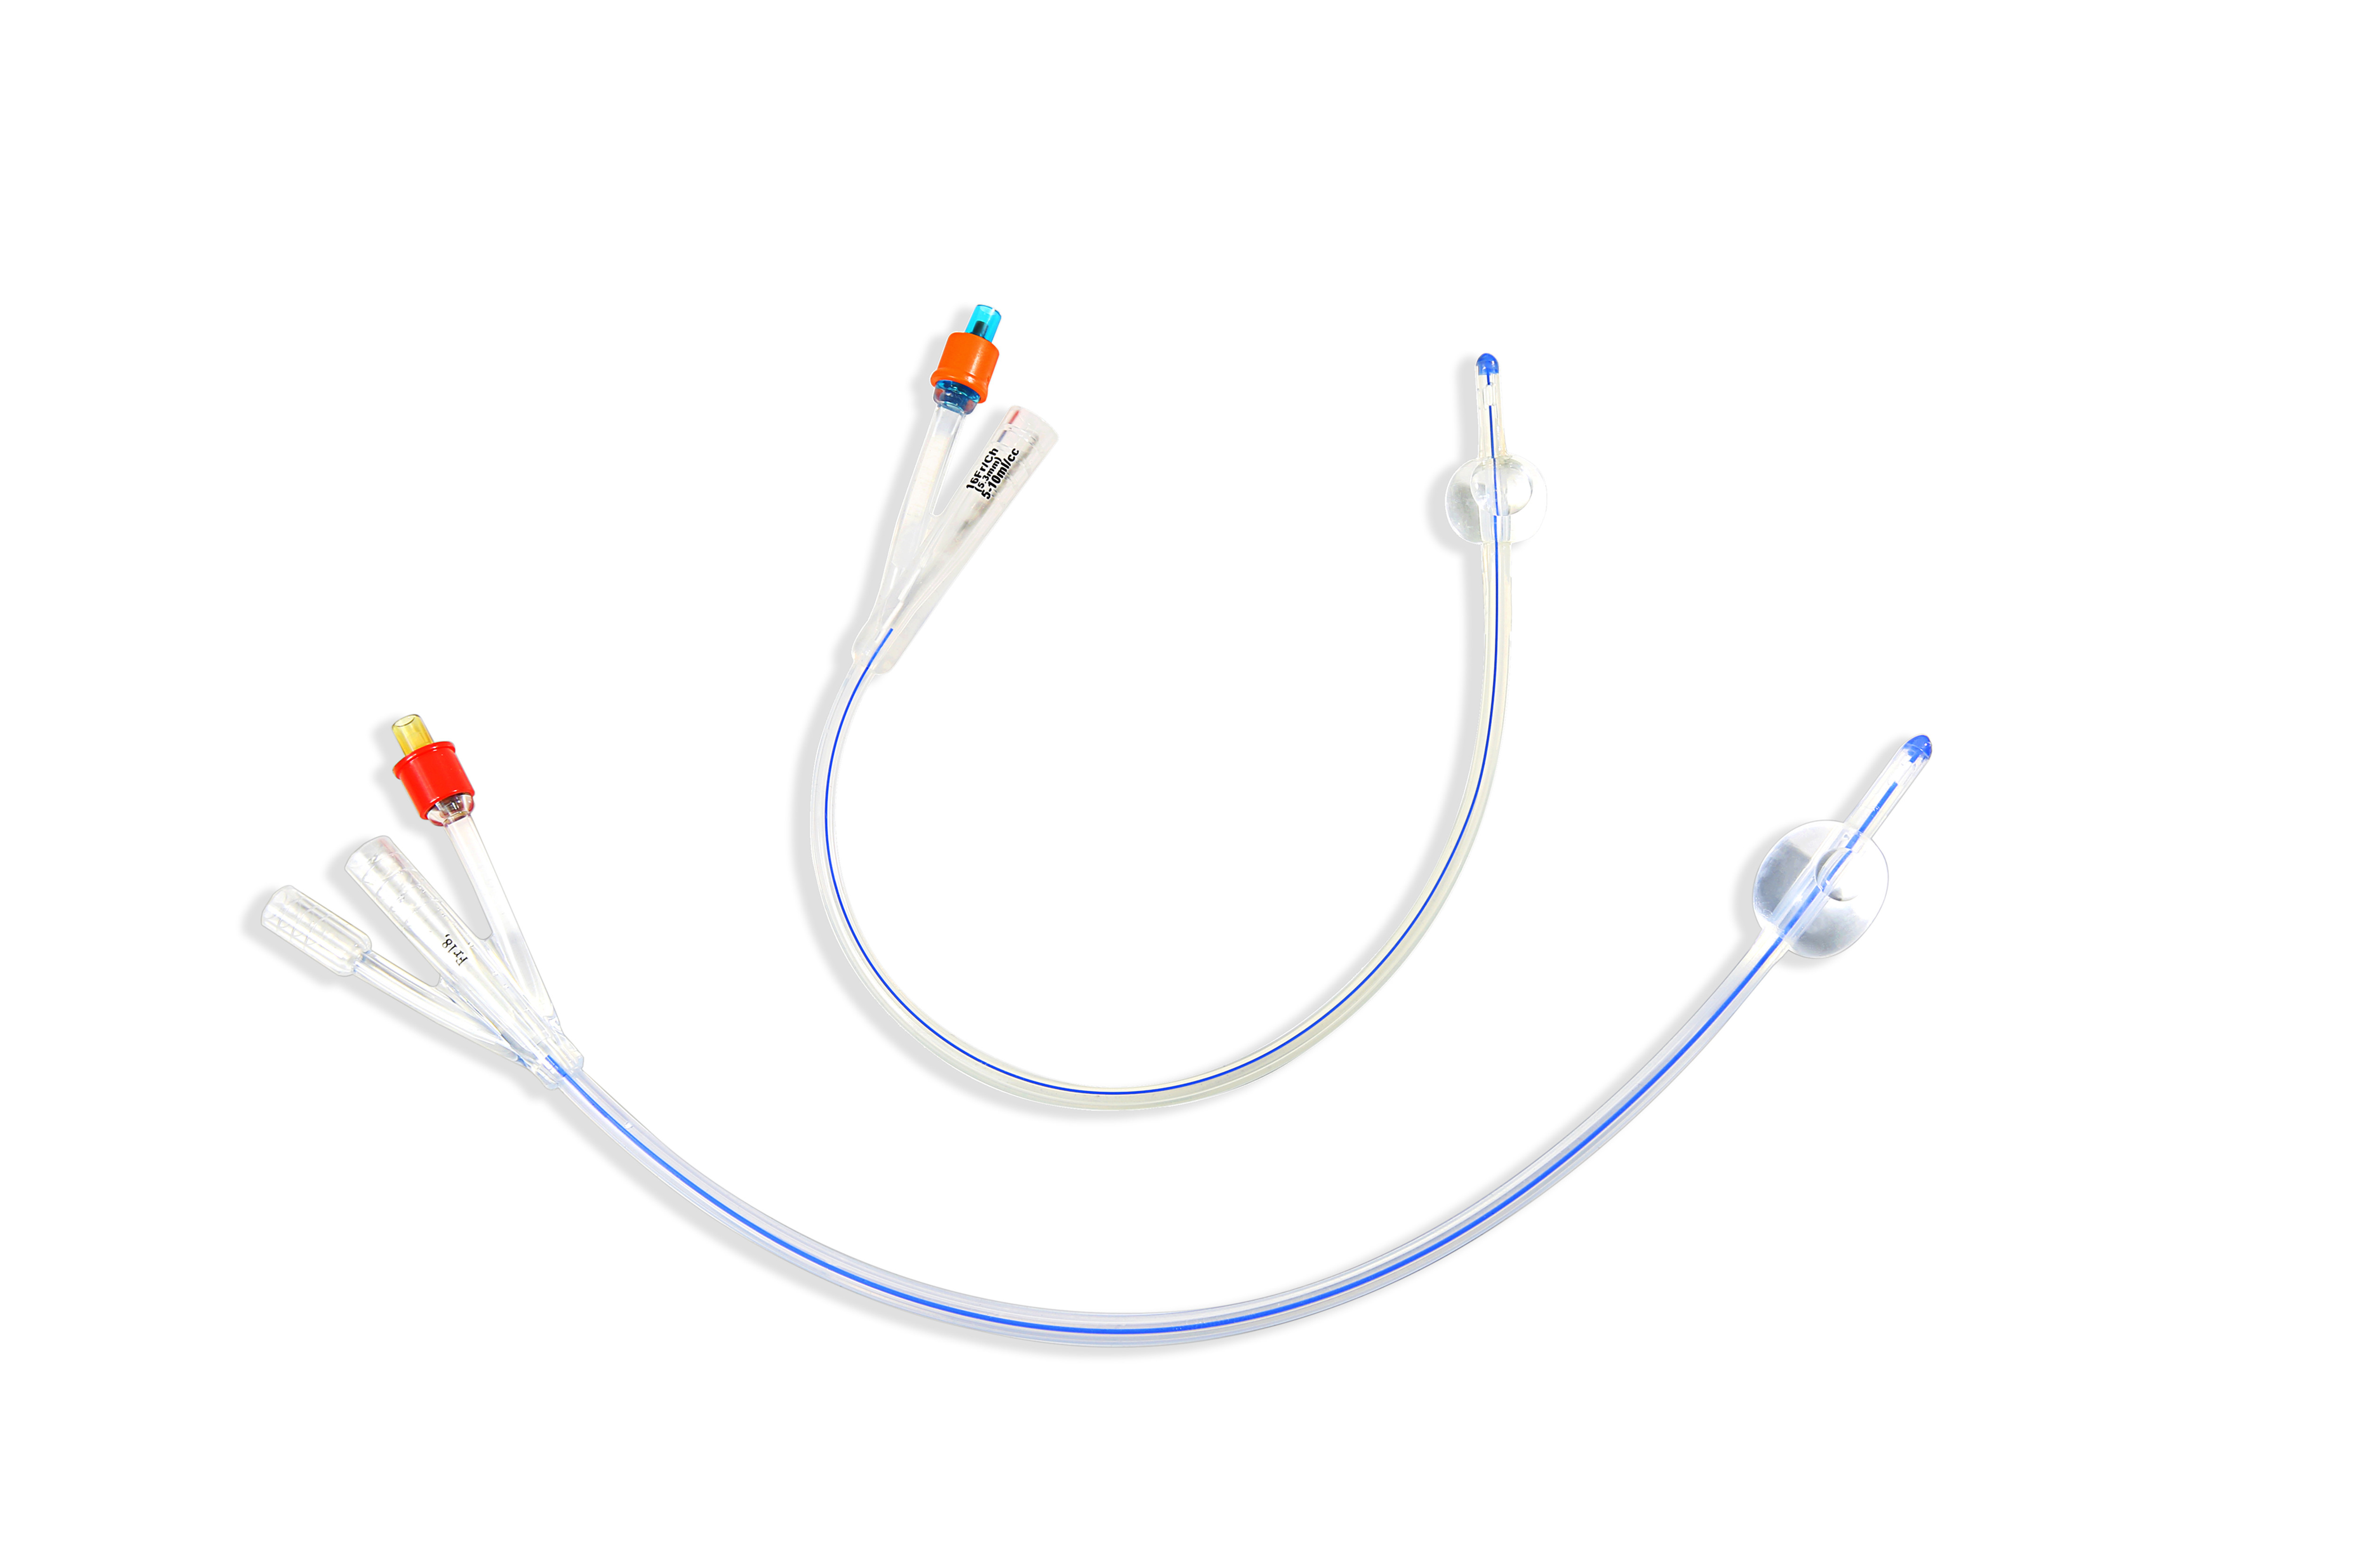

Urine Drainage Catheter Silicone Foley

The device is intended used for drainage and catheterization...